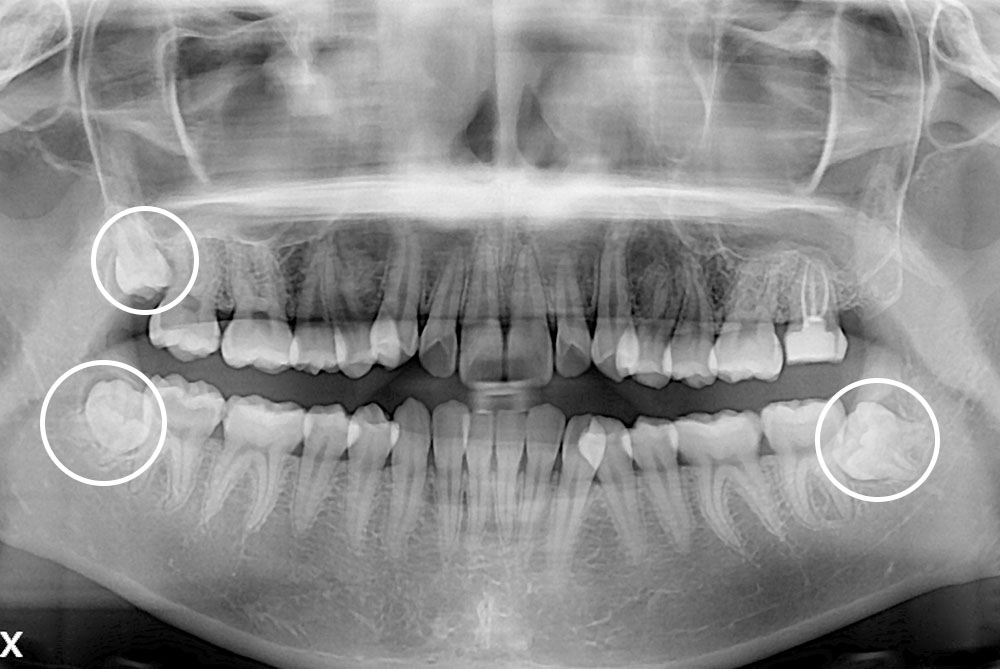

[사랑니] 매복 사랑니 발치

치료전 : 2017-02-01

치료후 : 2022-01-10

세종치과는 구강악안면외과학 박사이신 원장님이 발치하는 치과입니다.